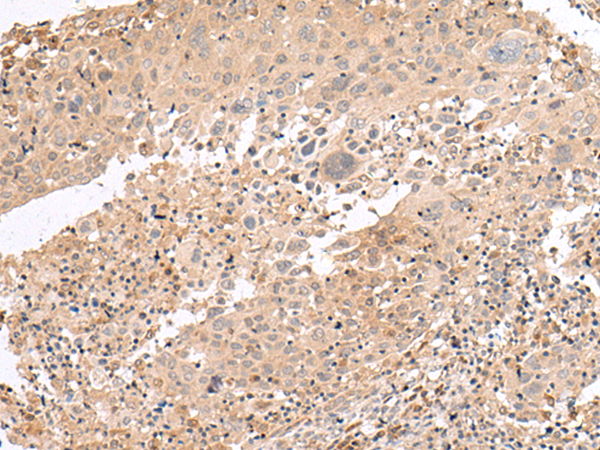

分类: 科研抗体货号: P06458别名: UCP4应用: WB,IHC反应种属: Human, Mouse, Rat

分类: 科研抗体货号: P06457别名: ILRA; CD127; IL7RA; CDW127; IL-7R-alpha应用: WB,IHC反应种属: Human